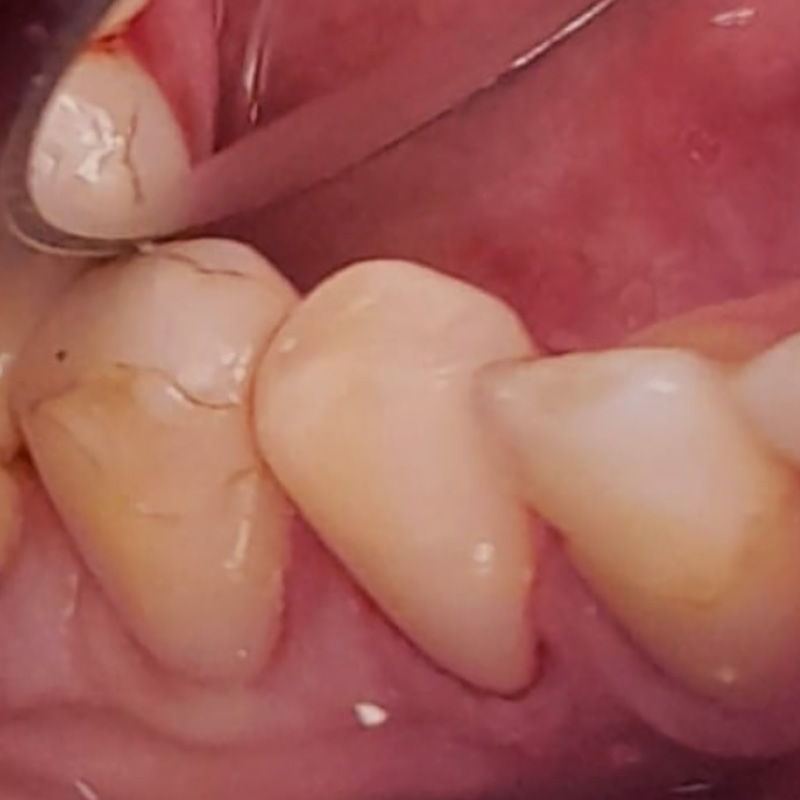

Пациентка обратилась в «Стоматологию Комфорта» с жалобой на отсутствие зубов верхней челюсти. По результатам обследования врач стоматолог-ортопед, хирург-имплантолог Мельников Алексей Владимирович назначил имплантацию по методу «all-on-4». По истечении 6 месяцев после операции проведено обслуживание условно-съёмного протеза. Также врач начал восстановление нижней челюсти коронками в комбинации с бюгельный протезом.

- восстановление нижней челюсти коронками в комбинации с бюгельным протезом.